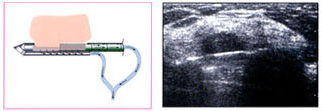

1 초음파 영상을 보면서 유방검사기 탐침을 병변부위에 위치시키면, 진공 System이 조직을 흡입합니다.

2 탐침 안쪽 바늘이 돌면서 전진하여 흡입한 병변조직을 잘라내고, 이 샘플조직은 수집장소로 옯겨집니다.

3 조직 채취가 끝나고 나면 조직을 떼어낸 자리에 Masker를 넣어 표시를 하고,

유방검사기 탐침을 뺀 후 반창고를 붙입니다.